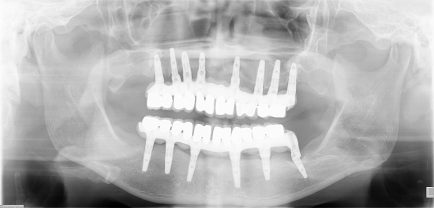

| 主訴 | 全顎治療希望、下の奥の歯が無いので全く噛めない。綺麗で噛めるようになりたい |

| 治療内容 | 下顎臼歯部欠損放置のため、臼歯部においてスペースがないため、全顎治療を行い咬合再構成を行う。 早期においてインプラント治療、咬合関係を模索した後、全顎にわたりセラミックによる補綴治療、その後メインテナンスに移行 |

| 治療費 | 5,410,000円(税込)(インプラントすべて含む) |

| 治療期間 | 1年8ヶ月 |

| 治療回数 | 80回 |

| 想定されたリスク | 食いしばり(パラファンクション)によるセラミックの破折、歯の破折 |